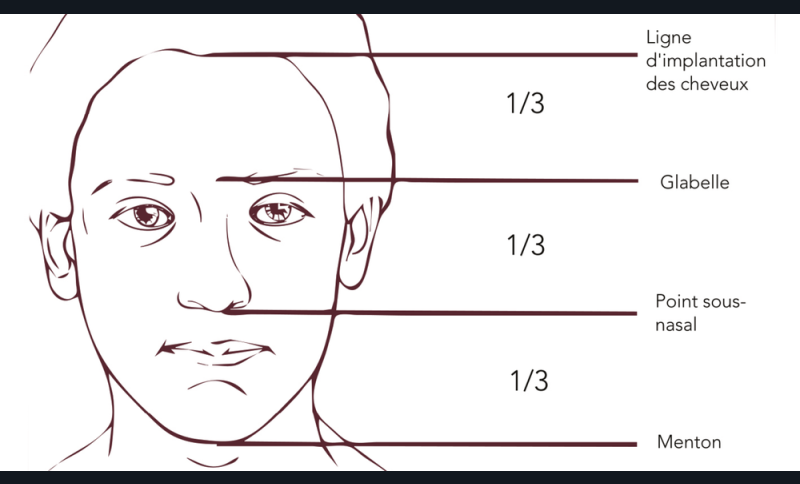

Harmonie du visage

Léonard de Vinci nous a donné un autre moyen de vérifier la DVO : vérifier l’égalité des étages supérieur, moyen et inférieur de la face [20,21]. Cette appréciation visuelle peut être complétée par une approche numérique en traçant les lignes de références de la face du patient. Cette technique doit être considérée avec réserve, et surtout en la pondérant avec les autres (fig. 21).

L’étage inférieur de la face (distance du point sous nasal au gnathion) a une dimension équivalente à [14,21] :